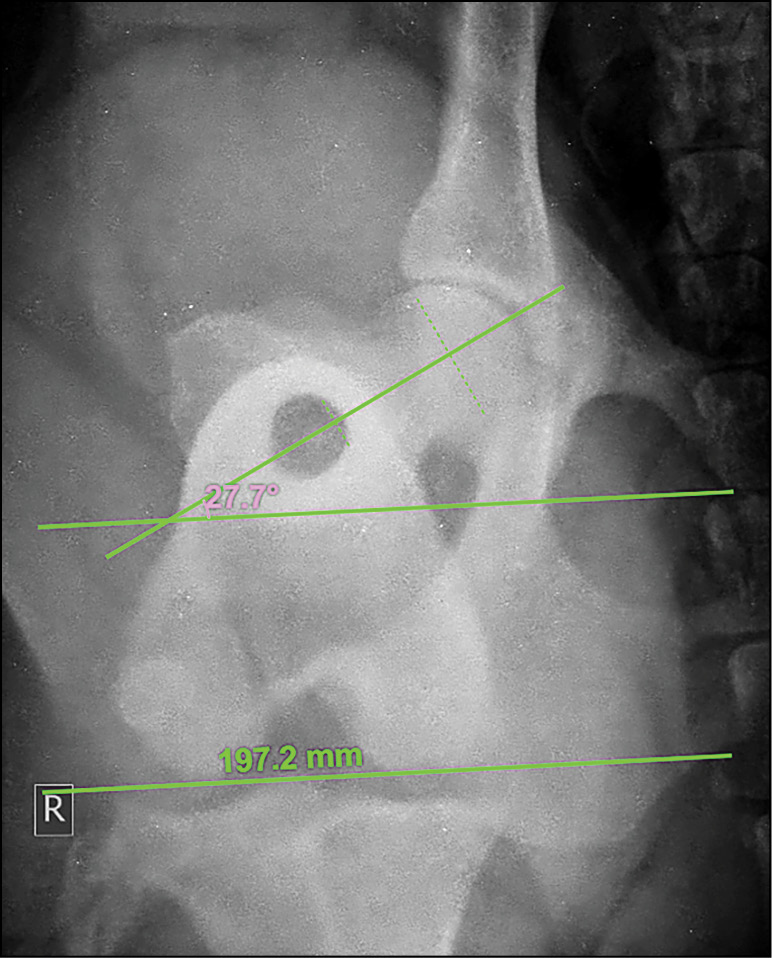

Osteotomia korekcyjna kości udowej

dół prostowniczy (łac. fossa extensoria); ryc. archiwum autorek

dół prostowniczy (łac. fossa extensoria); ryc. archiwum autorek